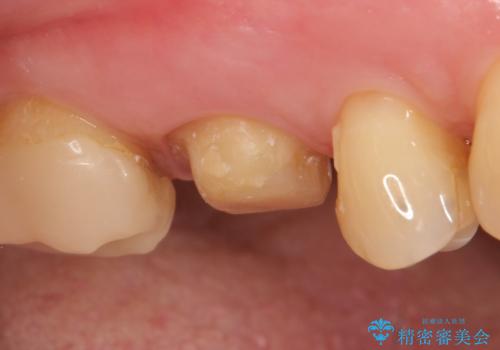

- 他院にて右上6の神経が死んでいるため根管治療が必要だと言われ当院にいらっしゃった方の症例です。

X線上で根尖病変を認めたため根管治療を行い、その後オールセラミッククラウンによる補綴を行いました